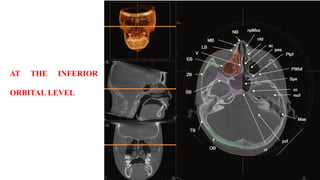

AT THE INFERIOR

ORBITAL LEVEL

• 62.